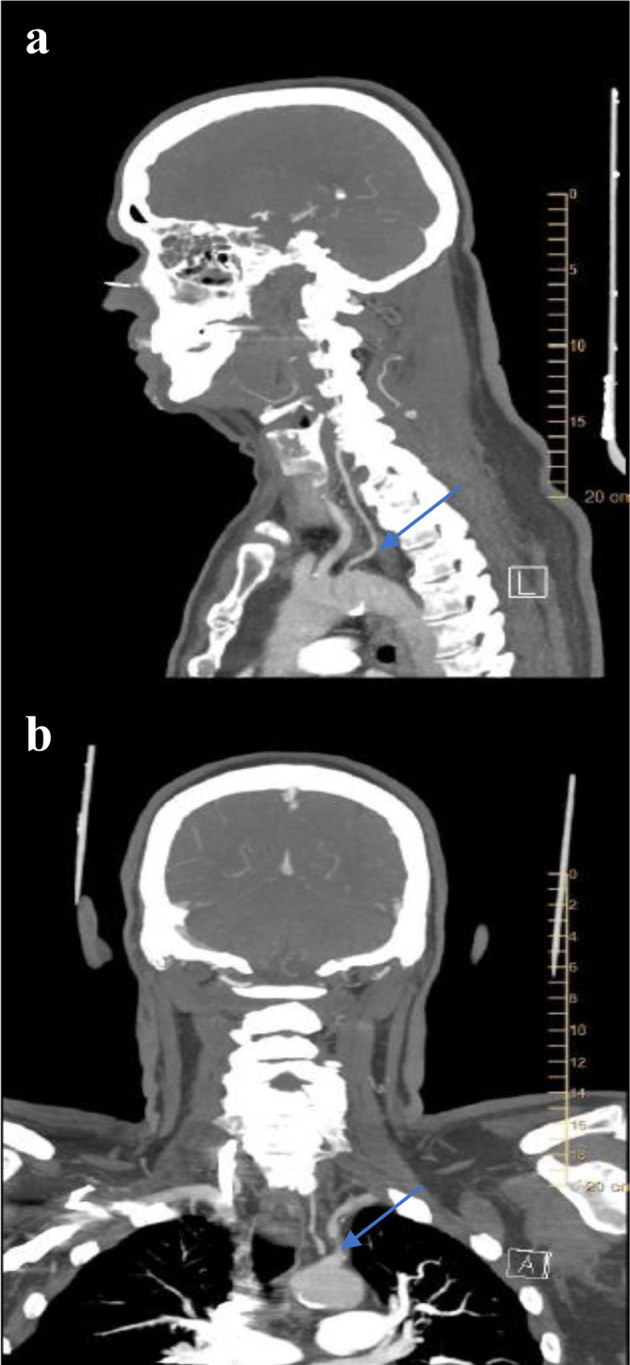

The subclavian steal syndrome (SSS) is defined by the reversal of flow in the ipsilateral vertebral artery in the setting of subclavian artery stenosis proximal to its origin. Here, we describe a rare case of left SSS with significant left subclavian artery stenosis associated with anomalous origin of the left vertebral artery (LVA) directly from the aortic arch in a patient presenting with signs of vertebrobasilar insufficiency and resolution of symptoms following angioplasty. Through this case, the authors try to emphasize the importance and the correct technique of using Doppler ultrasonography, and the importance of invasive angiography in understanding the mechanism of subclavian steal in patients with anomalous LVA origin.